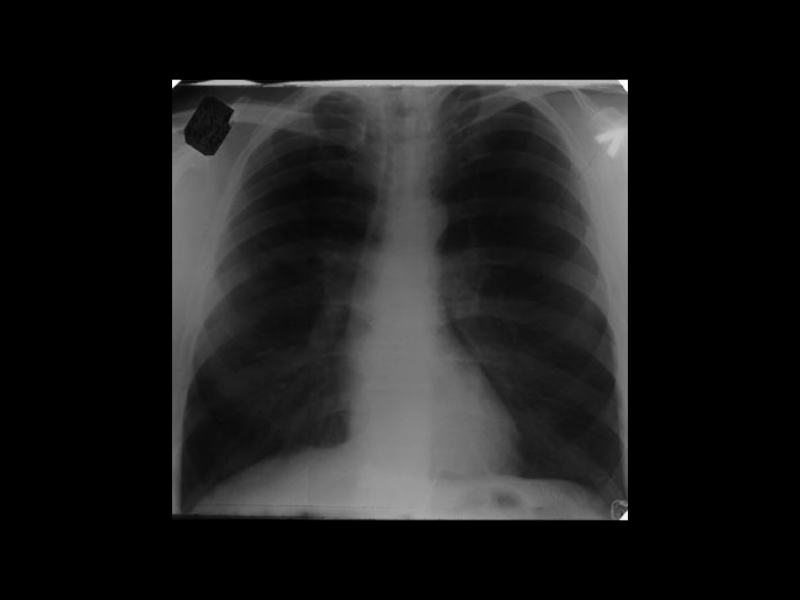

Центральный рак легкого

ЛУЧЕВАЯ ДИАГНОСТИКА РАКА ЛЕГКОГО

АКТУАЛЬНЫЕ ВОПРОСЫ РЕНТГЕНОЛОГИИЦентральный рак легкогоЛУЧЕВАЯ ДИАГНОСТИКА РАКА ЛЕГКОГО